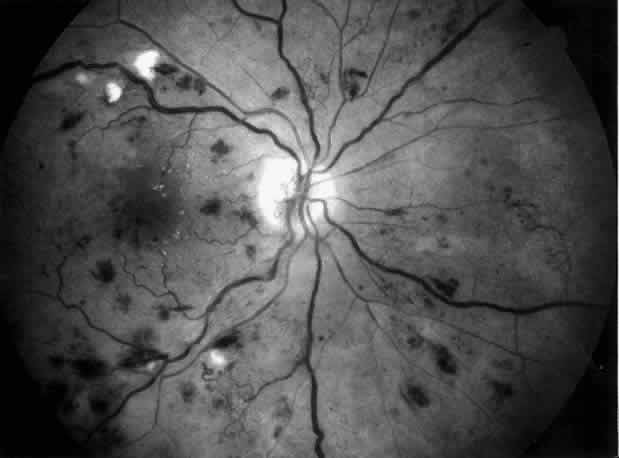

Diabetic retinopathy is characterized by increased vascular permeability leading to retinal edema and capillary closure leading to retinal ischemia and new vessel growth. With time, diabetic retinopathy occurs in nearly all diabetics; many will develop proliferative retinopathy. In patients with diabetic nephropathy, retinopathy is always present and proliferative retinopathy is common. However, 35% of patients with proliferative retinopathy have no signs of diabetic nephropathy, and these patients will probably never develop nephropathy.69,70 Retinopathy tends to deteriorate as renal failure develops, particularly in patients with poorly controlled blood pressure and in patients in whom no retinal treatment has been given before development of renal failure. Hypertension changes the funduscopic aspect and the course of background retinopathy by producing diffuse macular edema, cotton-wool spots, and numerous flame-shaped hemorrhages, particularly in the peripapillary area and along the main retinal veins (Fig. 5). In addition, hypertension accelerates the evolution of background to proliferative retinopathy. Treatment of hypertension and of end-stage renal failure will improve the retinopathy, particularly macular edema, and stabilize vision.68 It is currently accepted that preservation of vision correlates well with blood pressure control and that patients with end-stage renal disease suffering from diabetic retinopathy now enjoy an equivalent visual prognosis whether treated by dialysis or given a kidney transplant.71 Since the progression of diabetic retinopathy is independent of diabetic nephropathy and not reversed by treatment of nephropathy, further follow-up and treatment of diabetic retinopathy is imperative. Patients with persistent macular edema may benefit from macular photocoagulation. In diabetics with active proliferative retinopathy, panretinal photocoagulation and vitrectomy may improve the visual prognosis by inducing involutional retinopathy and by removing vitreous hemorrhages and vitreoretinal traction. Moreover, diabetic patients with end-stage renal disease are predisposed to cataract, which may require surgical intervention. The progress made in improving the visual prognosis in diabetic end-stage renal disease reflects the synergistic efforts made by internists and ophthalmologists and emphasizes the importance of team approach in preventing blindness.71

Fig. 5. Combined diabetic and hypertensive retinopathy in a 52-year-old patient with long-standing diabetes and end-stage renal disease. Note optic disc and retinal new vessels, diffuse retinal edema, numerous hemorrhages, and several cotton-wool spots along the main veins.